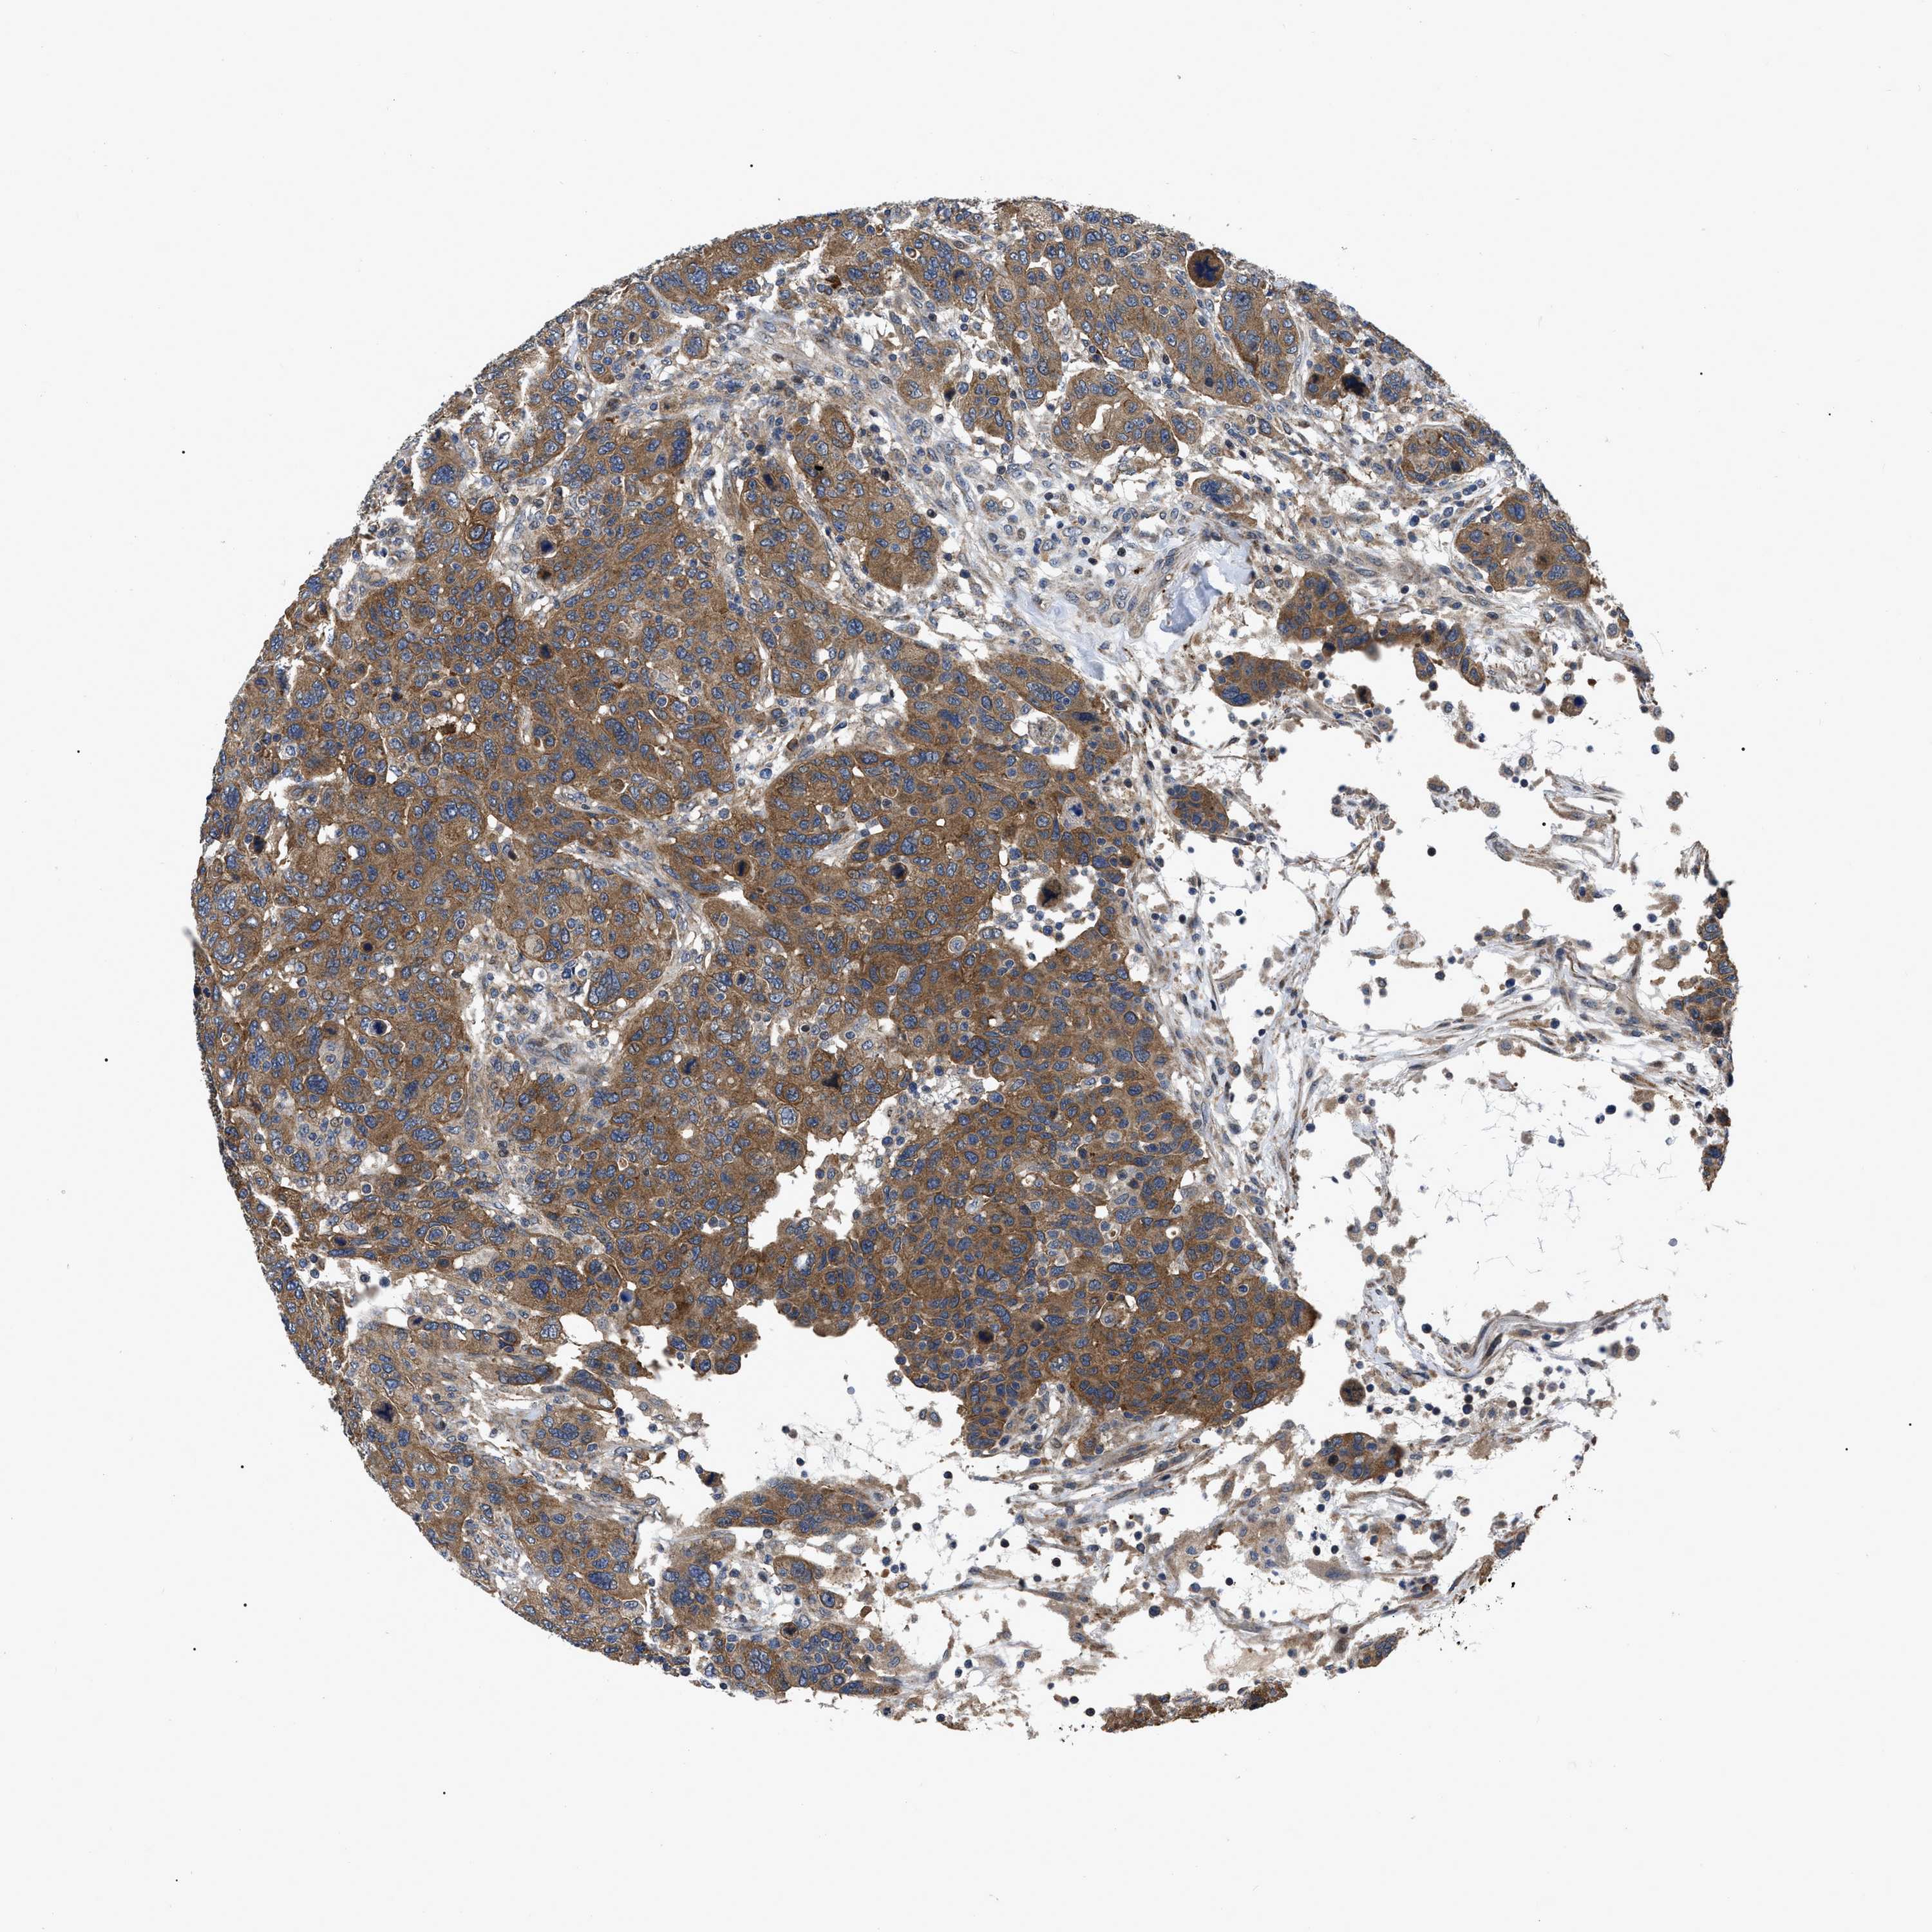

CANCER BREAST CANCER Show tissue menu

BRCA TCGA BRCA VALIDATION PROTEIN EXPRESSION